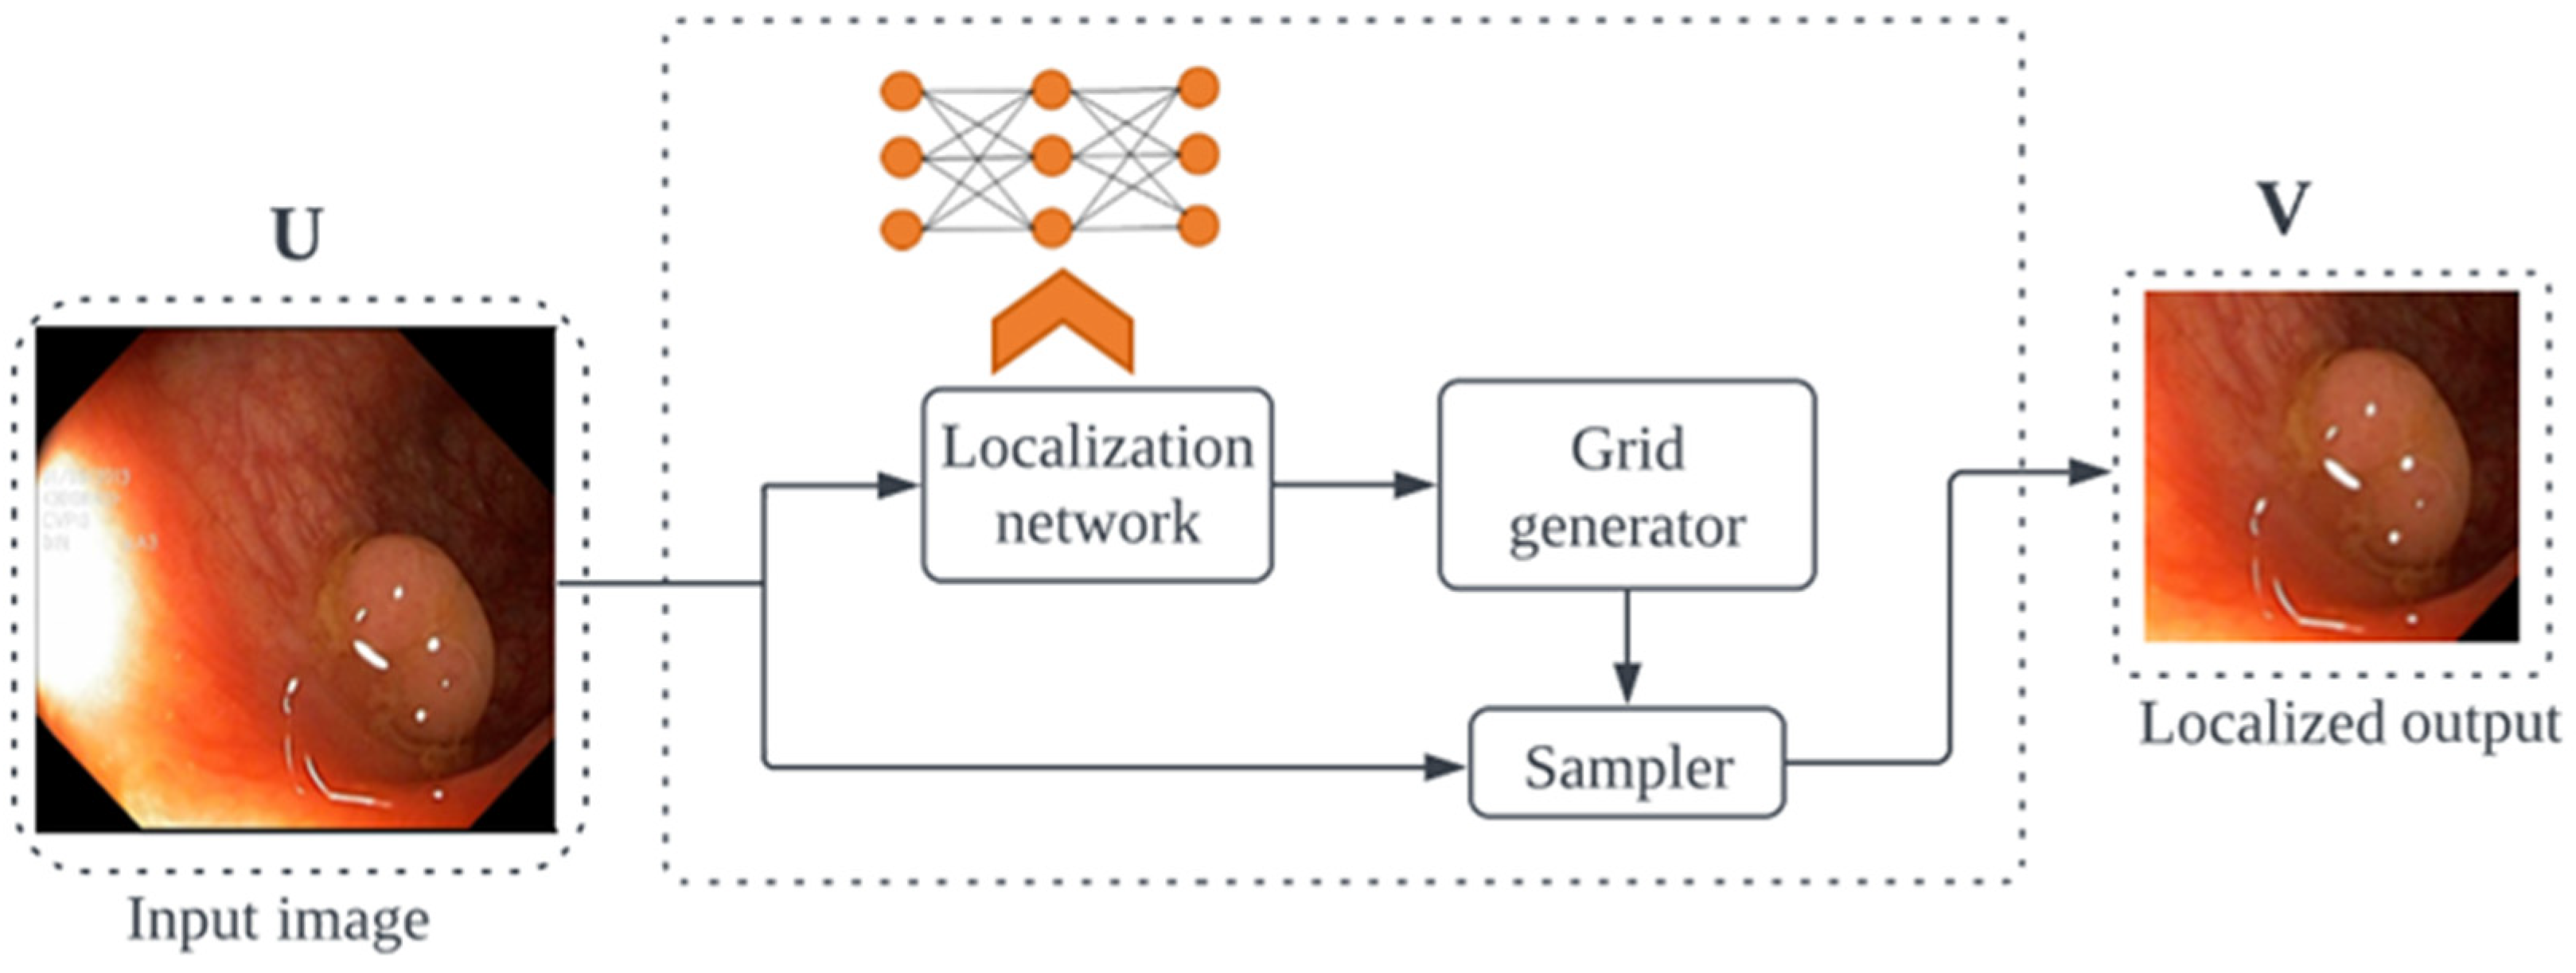

3.1.2. ViTCol Architecture

3.2. PUTS: Vision Transformer-Based Polyp Segmentation

3.2.2. PUTS Architecture